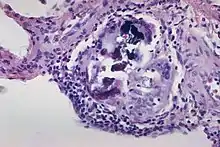

In this image there are multiple Schaumann bodies with crystalline inclusions.[1] Schaumann bodies are calcium and protein inclusions inside of Langhans giant cells as part of a granuloma.

1. USA, Yale Rosen from (2011-08-04), The crystalline inclusions that may be found within the giant cells in sarcoidosis and other granulomatous disorders consist mainly of calcium oxalate and well as some calcium cargbonate. In this image there are multiple Schaumann bodies closely associated with crystalline inclusions. In many cases the crystals appear to serve as a nidus around which Schaumann bodies are formed. H&E stain., retrieved 2021-12-10